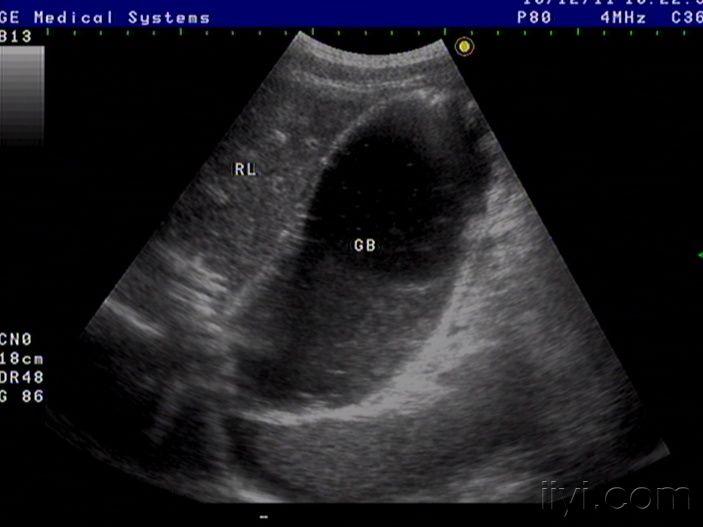

42岁女性患者,自觉腹胀一月余,未诉其它不适,月经规则,彩超中下腹部至盆腔左右各一包块如图,请老师看看像什么,以前没见过这样的这么大的包块

粘液性囊腺癌

是啊,网膜都已经广泛转移了,